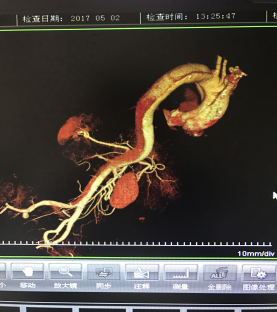

5月2號劉大伯照常早起干活,突然胸部劇烈疼痛,難以忍受,全身大汗,同時伴有右上肢發(fā)涼,他心想這次心絞痛比之前嚴(yán)重的多啊,趕緊叫上孩子到吉林國文醫(yī)院心血管內(nèi)科住院,患者長期高血壓病史,血壓一直控制不理想,大夫給他做了檢查,測左上肢血壓:82/45mmHg,右上肢血壓測不出,心率52次/分,右側(cè)肱動脈、尺動脈、橈動脈搏動消失,左側(cè)股動脈搏動較右側(cè)弱?!霸懔耍p側(cè)血壓差別這么大,是不是主動脈夾層了?”,接診大夫趕緊找來李主任,李主任反復(fù)詢問患者病情,表情突然凝重起來,患者胸痛這么明顯,血壓低的厲害,主動脈夾層的可能性很大。二話不說,李主任立即聯(lián)系影像科的醫(yī)生準(zhǔn)備做主動脈CTA,移動患者做檢查的過程大夫們非常小心,嚴(yán)密監(jiān)測患者血壓變化情況。兩個小時后結(jié)果出來了,主動脈夾層從升主動脈一直撕裂到左側(cè)髂總動脈?。?!

從開始學(xué)醫(yī)到現(xiàn)在已經(jīng)快9年了,主動脈夾層患者也見過一些,但像劉大伯這種危險類型的還是第一次見到,心里真的為他捏把汗,撕裂的主動脈隨時都有可能破裂,生命隨時可能終止,要知道主動脈夾層的死亡率非常的高,約50%的患者發(fā)病后48小時死亡,約90%的患者發(fā)病1個月內(nèi)死亡。

李主任詳細(xì)的與劉大伯的女兒交代了病情,手術(shù)是挽救生命的唯一辦法,為了劉大伯的一線生機(jī),我們積極聯(lián)系了我省權(quán)威的心血管外科,并做了詳細(xì)的匯報,兩家醫(yī)院對此非常重視,為劉大伯開通了綠色通道,安全的把他總到上級醫(yī)院,當(dāng)天便給他進(jìn)行血管置換及覆膜支架植術(shù)。他術(shù)后恢復(fù)的很好,后來劉大伯的女兒看望我們,感嘆道:沒想到國文醫(yī)院心內(nèi)科應(yīng)急能力這么高,在那么短的時間內(nèi)診斷明確,才給了我的老父親手術(shù)的機(jī)會。